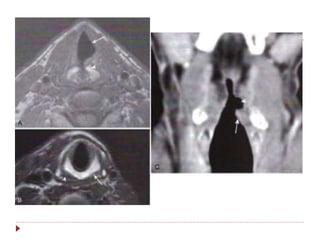

Laringe